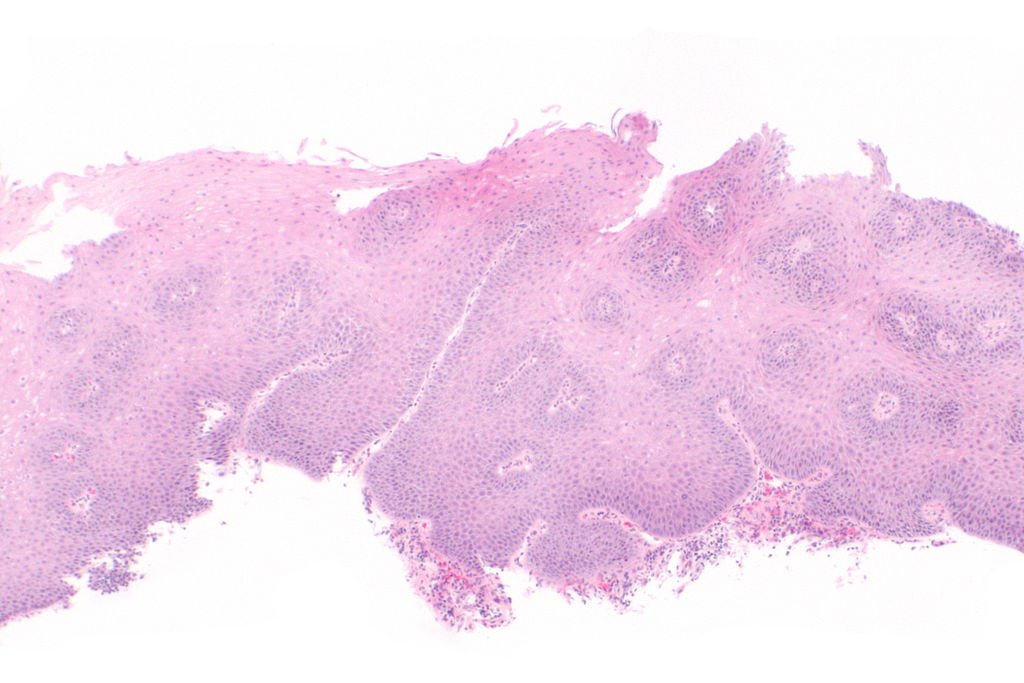

Endoscopia este cea mai bună metodă pentru depistarea unei forme severe de esofagită. În cazul în care medicul poate suspecta la un pacient o esofagită de reflux poate folosi endoscopia digestivă superioară pentru a fi sigur de acest diagnostic. Prin acest test de investigație clinică se pot descoperi cele 5 grade de esofagită.

În esofagita de gradul 1 apare o singură leziune izolată care afectează un fald al mucoasei și este ovală sau liniară. În esofagita de gradul 2 apar mai multe eroziuni care pot distruge mai multe falduri ale mucoasei acestui organ. În esofagita de gradul 3 sunt depistate mai multe leziuni circumferențiale. În esofagita de gradul 4 apar leziuni cronice pe esofag. În esofagita de gradul 5 este vorba despre așa numitul esofag Barret cu stricture mai mici și reepitelizare cu mucoasă cilindrică. Prin intermediul biopsiei (din zona de stenoză, de sub stricturi și de deasupra lor) se poate depista o formă ușoară de esofagită și astfel se stabilește un tratament corespunzător vindecării bolii.

Medicul folosește frecvent colecistoscintigrafia sau scintigrafia hepato-biliară ce ajută la analiza conținutului duodenal în stomac iar în plus indică și refluxul conținutului duodenal. O altă metodă este endoscopia digestivă superioară pentru stabilirea diagnosticului bolii de reflux gastro-esofagian. Endoscopia permite studiul tubului digestiv superior, observarea gastritei, a ulcerațiilor antrale, refluxului intestine-esofagian, refluxului excesiv duodeno-gastric, gastritei cronice. Biopsia face parte și ea din categoria testelor pentru diagnosticul acestei boli.